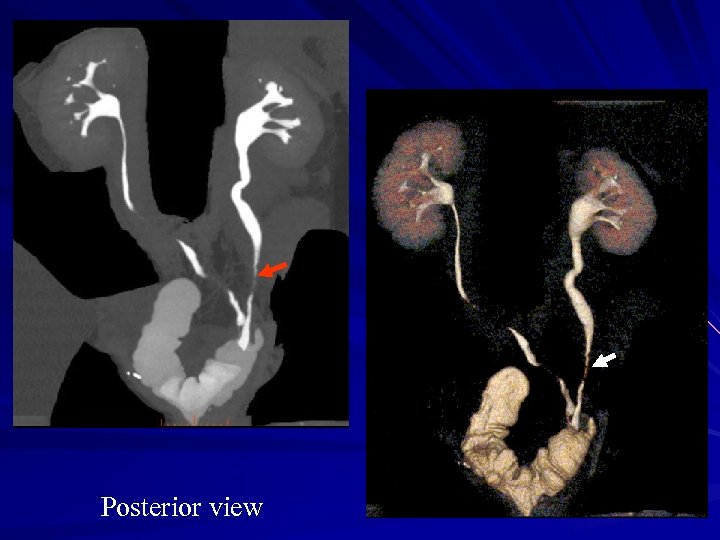

56 Y. O. man macrohematuria Rec. bladder TCC seen at cystoscopy Posterior view

Posterior view